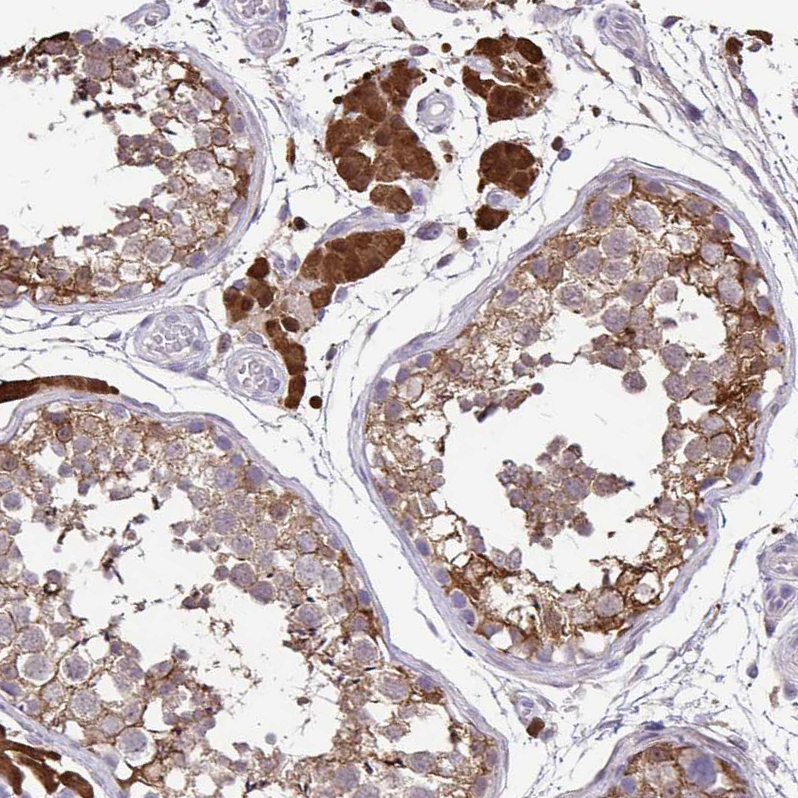

Immunohistochemical staining of human prostate shows moderate cytoplasmic positivity in glandular cells.